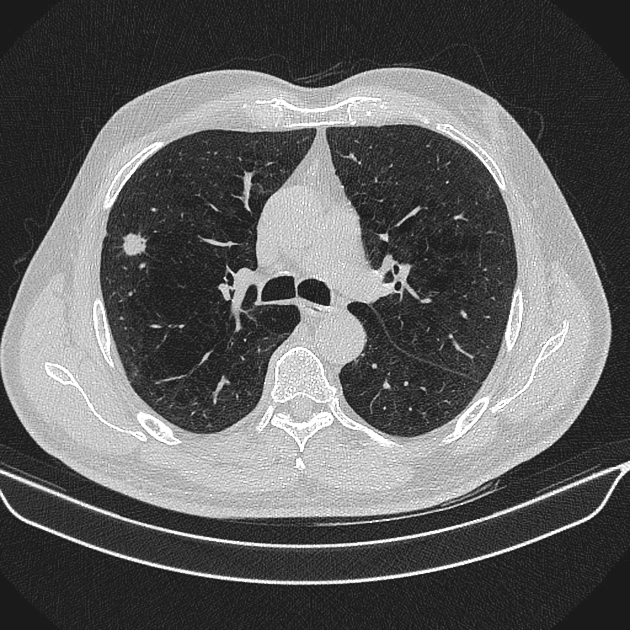

U phổi - Ảnh 3

U phổi

» Thông tin: Nam giới – 70 tuổi.

» Lâm sàng: Ho / Tiền sử hút thuốc lá.

# Ung thư biểu mô tuyến (Adenocarcinoma).